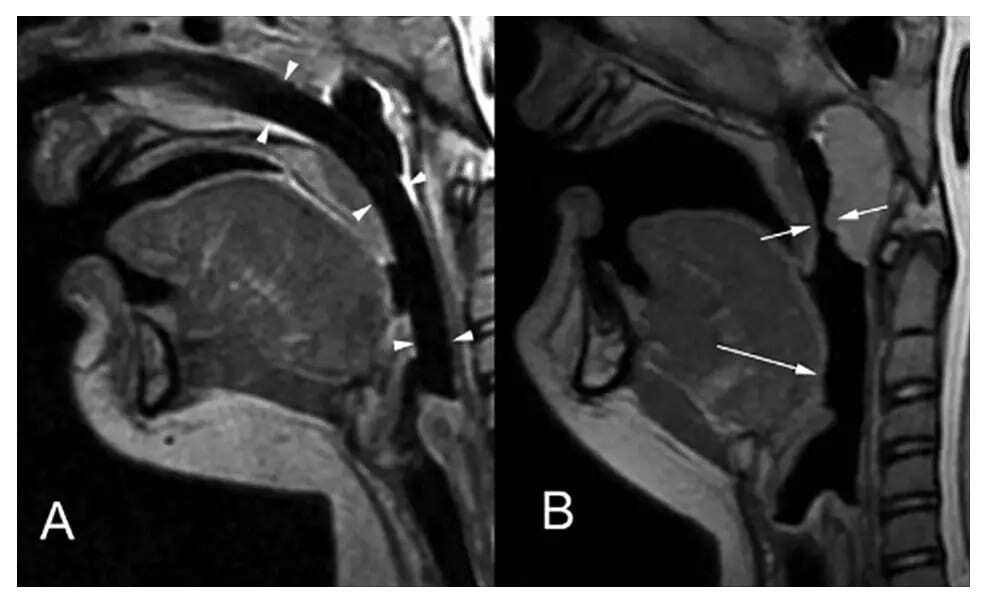

CT showing airway being maintained with NPA

Measure NPA from the nostril to the earlobe or tragus.

Use caution when inserting a nasopharyngeal airway in patients with a possible craniofacial injury or basilar skull fracture as studies have reported iatrogenic injuries when inserting the nasopharyngeal airway.